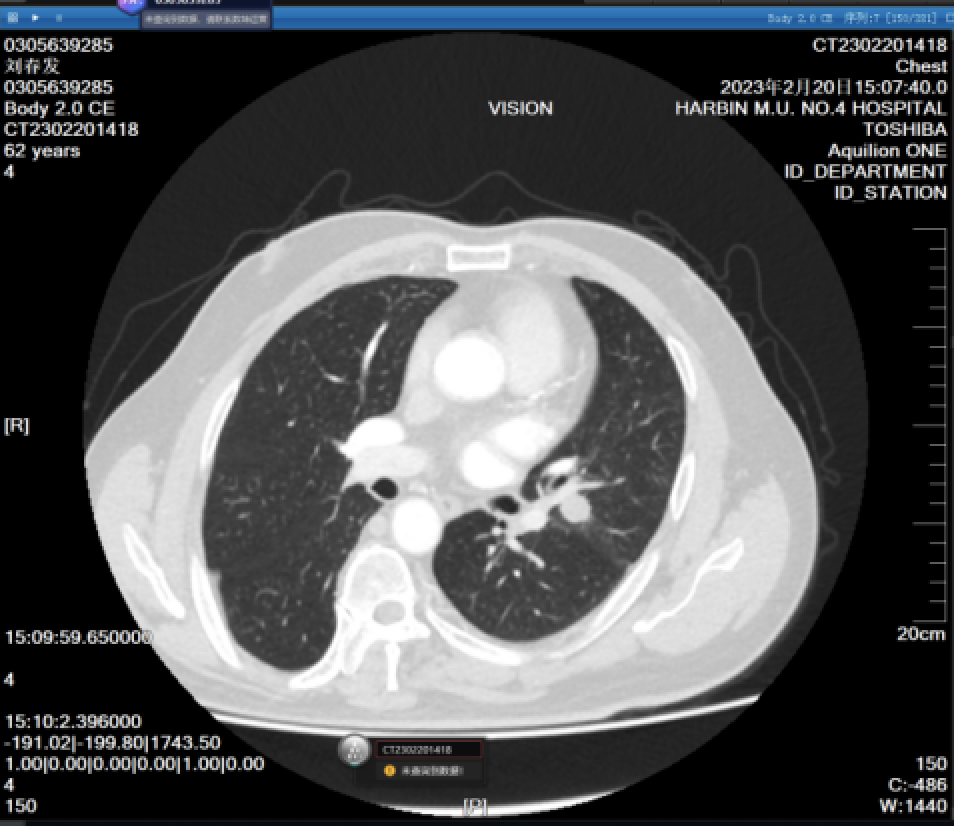

image.png

图四:部分实性磨玻璃结节

磨玻璃阴影是指肺内局限性密度增高区,边界清晰或模糊,透过该阴影仍可分辨正常肺结构,称为磨玻璃阴影(GGO)或磨玻璃结节(GGN)。对于不含软组织成分的磨玻璃状密度区,首选术语“纯磨玻璃结节”来描述。如果磨玻璃密度区含实性成分使肺结构模糊不清,则称为部分实性磨玻璃结节。在文献中,纯磨玻璃结节和部分实性磨玻璃结节被归类在亚实性结节中。